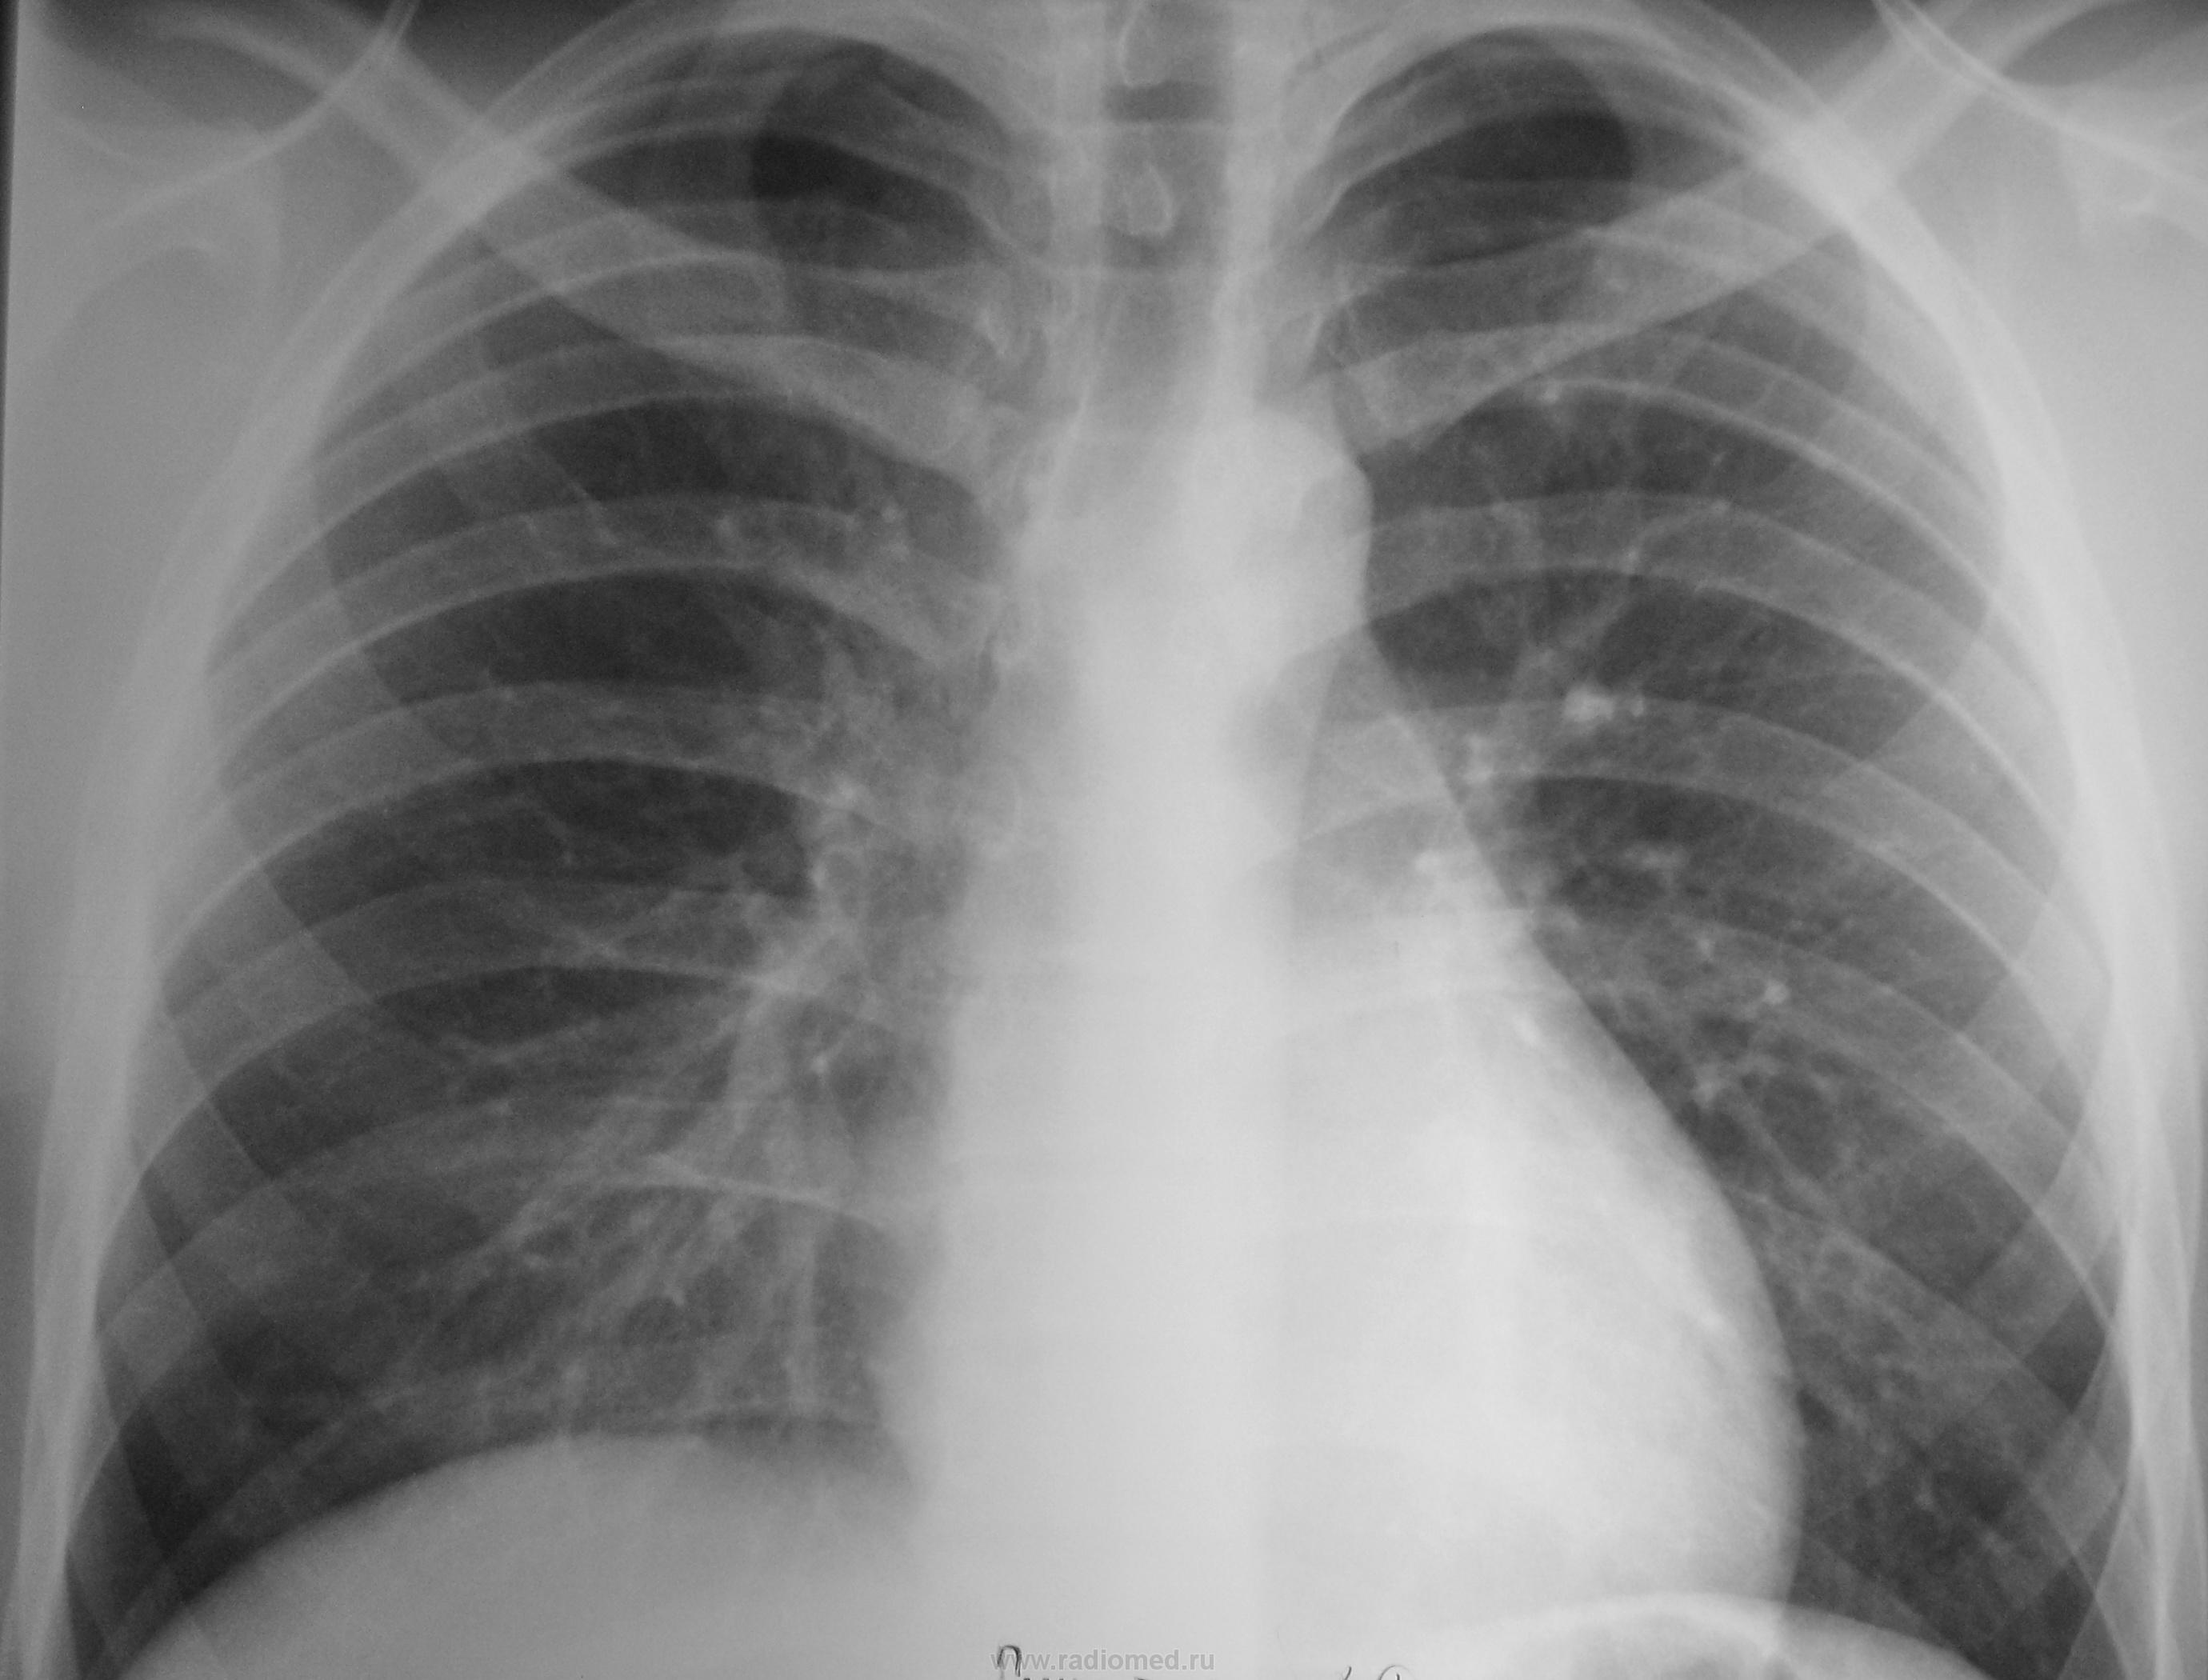

Случай №2 Женщина пришла на снимок ОГК для оформления стац. лечения панкреатита. Справа в надключичной зоне определяется небольшой очажок. Направил на консультацию, вернее написал в заключении.

Случай №2. Покрутил бы на скопии. Что-то присутствует.

Случай №2 Согласен с Бондаренко